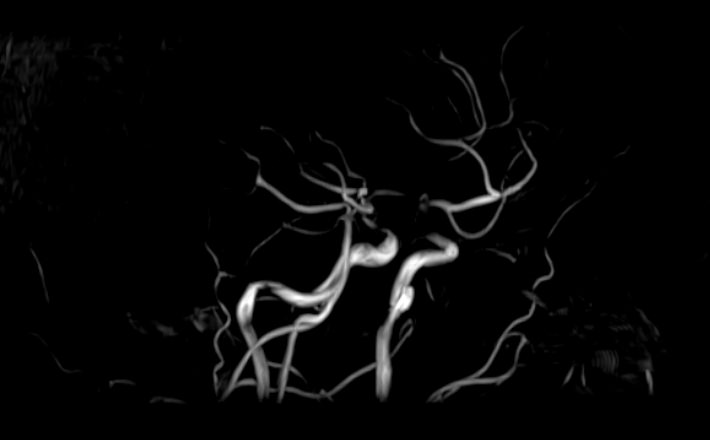

Кроме того, в области шеи проходят крупные кровеносные сосуды, кровоснабжающие все структуры головного мозга и мягких тканей головы. К ним относятся плечеголовной ствол, сонные и позвоночные артерии, которые далее в полости черепа соединяются между собой в Виллизиев круг. Это анатомическое образование позволяет компенсировать мозговой кровоток при патологических состояниях.

Часто различные нарушения в шейном отделе позвоночника приводят к ухудшению кровоснабжения головного мозга. Опухоли и дегенеративно-дистрофические заболевания шейного отдела позвоночника могут нарушать работу головного мозга. Атеросклеротические бляшки в сосудах шеи могут стать причиной преходящих нарушений мозгового кровообращения (транзиторных ишемических атак) и привести к развитию инсульта. Поэтому важно в комплексе детально визуализировать эти анатомические структуры вместе с оценкой состояния кровеносной системы головы и шеи.

• участки сужения, извитость, образование петель и перегибов сосудов;

• нарушения оттока крови за счет тромбообразования в венозном русле;

• ангиомы, сосудистые мальформации;